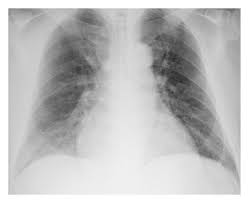

Cardiomegaly definition x ray. An enlarged heart cardiomegaly isn t a disease but rather a sign of another condition. Less severe forms of cardiomegaly are referred to as mild cardiomegaly. Maximal horizontal cardiac diameter. In equivocal cases the cardiothoracic ratio ctr can be easily calculated on a pa chest x ray.

Q fever endocarditis in hiv infected patient. It is not a disease but a sign of another condition. Chest x ray showed cardiomegaly and congestive heart failure. Cardiothoracic ratio is measured on a pa chest x ray and is the ratio of.

Cardiomegaly is easily visualized on chest x ray. At autopsy cardiomegaly with right atrial and ventricular dilation was identified. Therefore medications are prescribed to such affected individuals and they may have to take them for the rest of their lives. A useful measurement on x ray is the cardio thoracic ratio which is the transverse diameter of the heart compared with that of the thoracic cage these diameters are taken from pa chest x rays using the widest point of the chest.

Maximal horizontal thoracic diameter inner edge of ribs edge of pleura figure 2. X ray presentation of cardiomegaly most people are able to recover normal heart functions but only if the condition is detected early after which it is not possible to repair the damage. An x ray of the chest helps one to detect any kind of enlargement of the heart. Other findings on chest x ray can help to determine the specific chamber that is contributing most to the enlargement of the heart.

If the heart is enlarged on an x ray other tests will usually be needed to find the cause. Tap on off image to show hide findings. The ctr measures the width of the cardiac silhouette and the thoracic. X ray images help see the condition of the lungs and heart.

Cardiomegaly is an enlarged heart. In most cases merely eye balling a chest x ray will be sufficient in detecting cardiomegaly as the heart is either clearly normal in size or clearly abnormally enlarged. Other tests are then needed to diagnose the condition that s causing the heart to be enlarged.